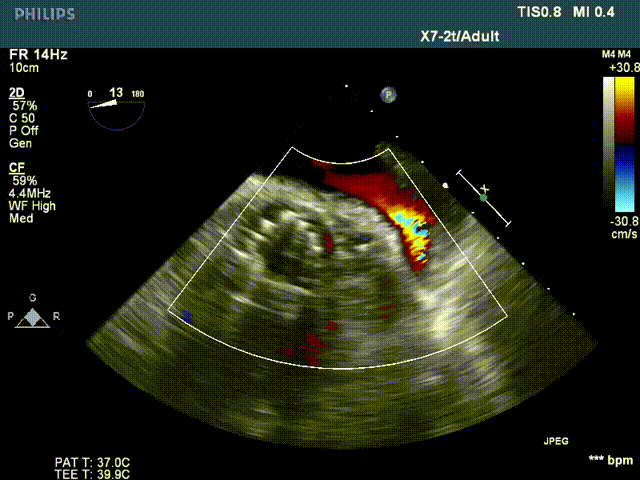

超声影像

瓣膜工作状态良好,极微量瓣周漏

Vmax 1.75m/s,PG 14mmHg

TEE影像,烟囱支架显影清晰,支架内血流通畅